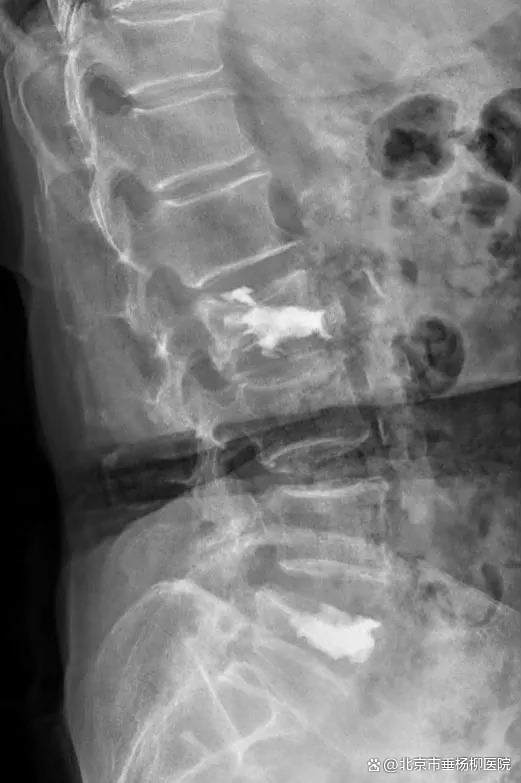

经过3个小时的手术,患者手术顺利,椎体内骨水泥弥散良好,椎管内神经减压彻底。术后患者恢复良好,当天即感觉疼痛缓解。经过2天的术后治疗,患者已经可以正常行走。术后3天,患者平安出院,后续接受康复治疗。

▲术后X线,椎体内骨水泥弥散良好